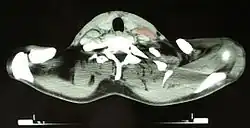

After Hodgkin lymphoma is diagnosed, a person will be staged by undergoing a series of tests and procedures that will determine what areas of the body are affected. These procedures may include documentation of their histology, a physical examination, blood tests, chest X-ray radiographs, computed tomography (CT)/positron emission tomography (PET)/magnetic resonance imaging (MRI) scans of the chest, abdomen and pelvis, and usually a bone marrow biopsy. PET scan is now used instead of the gallium scan for staging. On the PET scan, sites involved with lymphoma light up very brightly enabling accurate and reproducible imaging.[34] In the past, a lymphangiogram or surgical laparotomy (which involves opening the abdominal cavity and visually inspecting for tumors) were performed. Lymphangiograms or laparotomies are very rarely performed, having been supplanted by improvements in imaging with the CT scan and PET scan.[17]